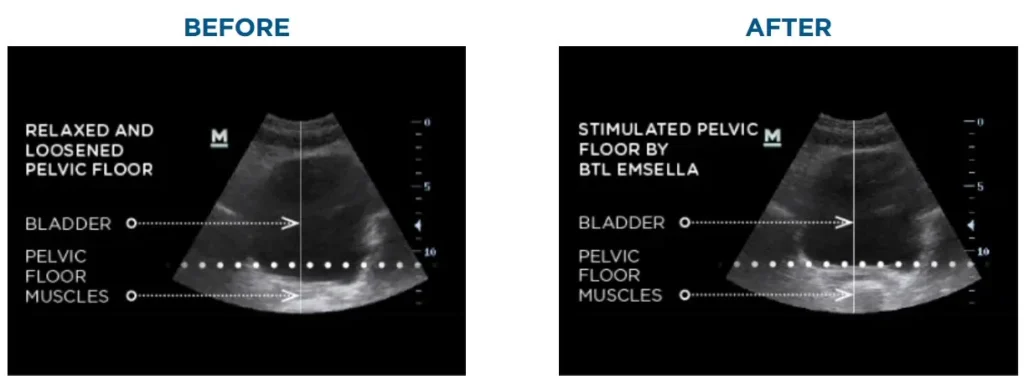

Emsella is an advanced, FDA-cleared treatment that restores pelvic muscle strength through pelvic floor therapy. Using High-Intensity Focused Electromagnetic (HIFEM) technology, the device stimulates thousands of supramaximal muscle contractions in just one session, something traditional exercises can’t match.

Emsella uses electromagnetic technology to contract and strengthen pelvic floor muscles in a way that’s impossible to achieve voluntarily. Here’s what the treatment process looks like: